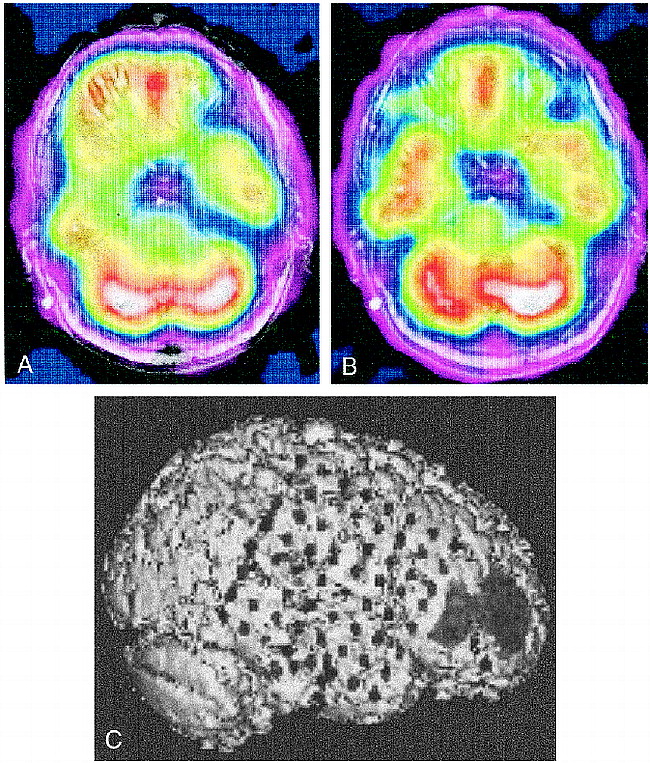

Figure 3 shows coregistered ictal and interictal SPECT scans in patient 2. Interictal scans show hypoperfusion in the right temporal region (Fig 3A), while ictal scans show symmetrical perfusion of the temporal lobes (Fig 3B). There was an area of ictal hyperperfusion in the right frontal region; therefore, the SPECT scans suggested perfusion changes in both the right temporal and right frontal regions. Triple-technique coregistration (Fig 3C), segmenting the ictal SPECT scan to highlight the area of hyperperfusion in the right frontal region, shows placement of subdural strip electrodes over the areas of perfusion change in the right temporal and frontal regions and a 64-electrode subdural grid over the right frontotemporal region. EEG results showed all seizures originated from the right subtemporal subdural strip electrodes with fast propagation to the right anterior frontal region. After partial temporal lobectomy, the patient has remained seizure-free during 20 months of postoperative follow-up.

A, Interictal coregistered MR-SPECT scan with right temporal hypoperfusion.

B, Ictal coregistered MR-SPECT scan shows symmetrical bitemporal perfusion. This represents a relative increase in cerebral blood flow to the right temporal region during the seizure. There was ictal hyperperfusion in the right frontal region as well.

C, Triple-technique coregistration shows subdural strip electrodes over the right temporal and frontal regions in relation to the area of ictal hyperperfusion in the right frontal region. EEG recordings localized all seizures to the right temporal region.

We relied on visual interpretation of interictal and ictal SPECT scans to determine the area of hyperperfusion. We then manually segmented the region of involvement using intensity thresholding. Recent studies indicate that computer-aided subtraction of the interictal from the ictal SPECT scans significantly improves the usefulness of SPECT in localizing the surgical seizure focus (10, 11). This technique effectively shows differences in interictal and ictal perfusion patterns. Patient 2 (Fig 3) represents a case in which differences in interictal and ictal perfusion patterns localized the area of seizure onset. The interictal study showed a hypoperfused right temporal region, while the ictal study showed normal symmetrical perfusion. The right frontal region showed ictal hyperperfusion, which correlated with EEG propagation to that area. Use of computer-aided subtraction of the interictal from ictal SPECT scans with our technique, rather than using visual SPECT interpretation alone, may allow for more accurate placement of subdural electrodes to confirm the epileptogenic zone.